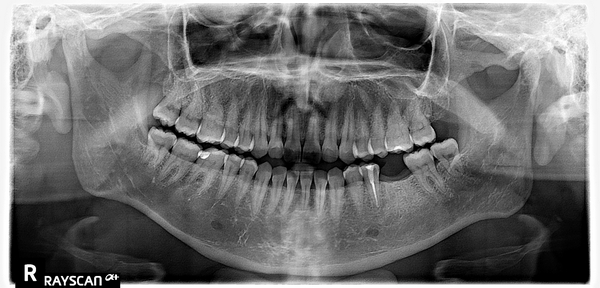

- Провели 3Д КТ обследование 2500 ₽.

- Осмотр и изучение 3Д снимков показал хорошее состояние полости рта, отсутствие кариозных полостей и каких либо воспалительных процессов.

- После внимательного изучения 3Д КТ снимков пациентке предложено провести имплантацию корейской системой OSSTEM, средней ценовой категории, с установкой коронки из диоксида циркония.

- В ходе осмотра состояние полости рта было хорошее, зубы рядом с отсутствующим были сохранены и не поражены кариесом.

После изучения снимков и учитывая пожелания пациента составили 2 варианта лечения.